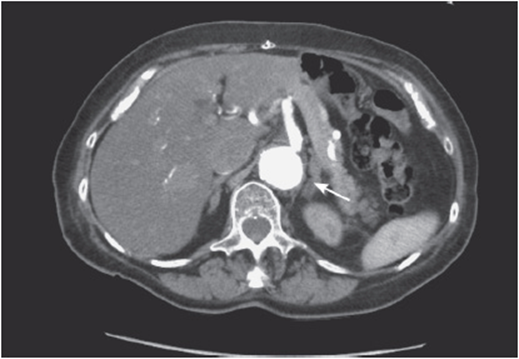

xi. Check the aorta and its branches:

• Follow the aorta from the diaphragm level, identifying sequentially the celiac artery, the superior mesenteric artery, the renal arteries, the inferior mesenteric artery, and the aortic bifurcation (see Figure 56-11).

Figure 56-11. Celiac artery at its origin from the aorta.

• Look for intraluminal filling defects or abrupt cutoffs, especially when mesenteric ischemia is suspected.